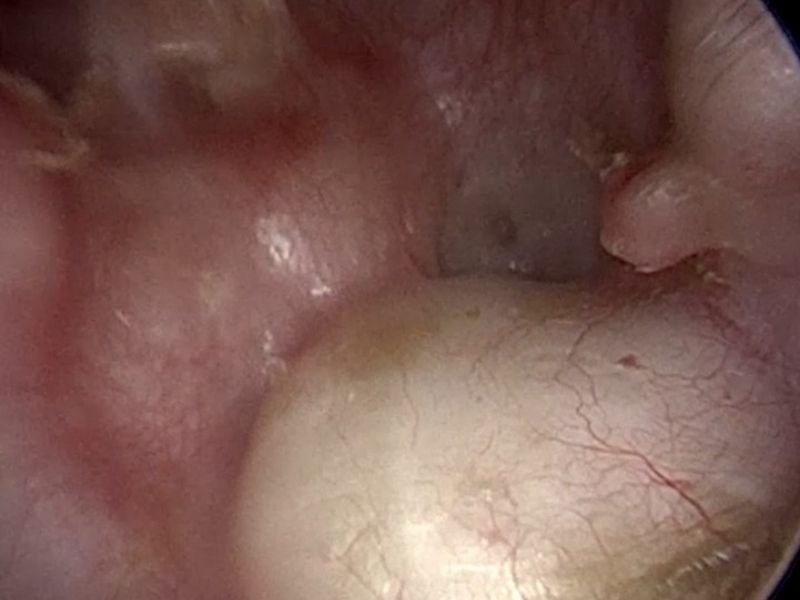

A estapedectomia é um procedimento cirúrgico que substitui o estribo, um dos ossículos do ouvido médio, por uma prótese. Esse tratamento é indicado para pacientes com otosclerose avançada, que não obtiveram sucesso com outras abordagens, como o uso de aparelhos auditivos. A cirurgia permite restaurar a condução sonora, proporcionando uma melhora significativa na audição.

Diferença Entre Estapedectomia e Estapedotomia

• Estapedectomia: Remoção completa do estribo.

• Estapedotomia: Substituição parcial do estribo por uma prótese.

Ambos os procedimentos são realizados para tratar otosclerose, e a escolha depende do quadro clínico.